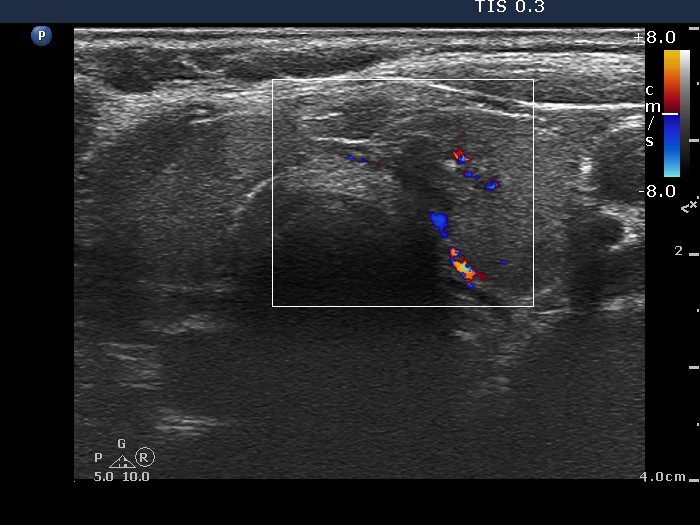

100 consecutive cases of papillary cancer - case 028 (ultrasonographic picture 5)

Right lobe, longitudinal scan

Left lobe, transverse scan, color Doppler mode. The vascularization is not specific.